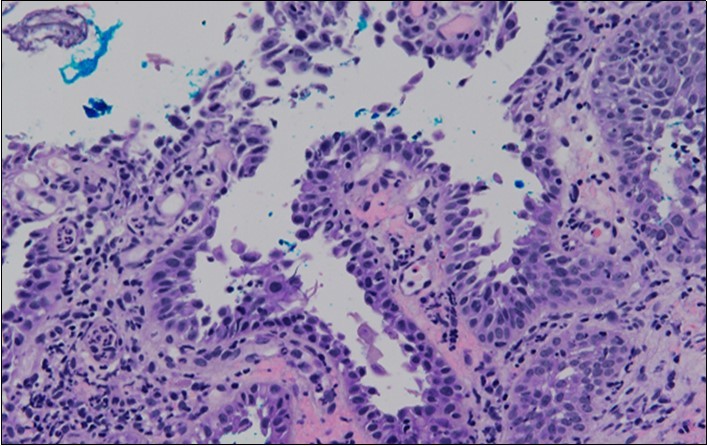

HPV test was negative for high risk subtypes of HPV. The punch biopsy specimen comprised a piece of inflamed cervical tissue in which the transformation zone was represented. The cervical tissue was covered by metaplastic and hyperplastic squamous epithelium showing intraepidermal suprabasal blister formation with acantholysis. Well vascularised dermal papillae lined residual basal cells giving rise to a tombstone appearance were present. There was no evidence of HPV, CIN, CGIN or invasive malignancy.

She was discussed at the hospital cyto-pathology conference to clarify the diagnosis. The original cytological smear specimen was reviewed, with features of bi-nucleation and koilocytosis consistent with LSIL. The cervical biopsy was also reviewed, confirming typical features suggestive of cervical pemphigus. (Figure 4a, Figure 4b, Figure 4c)

Figure 4b.Prominent acantholysis identified

Figure 4c.Well vascularised dermal papillae with residual basal layer giving rise to tombstone appearance